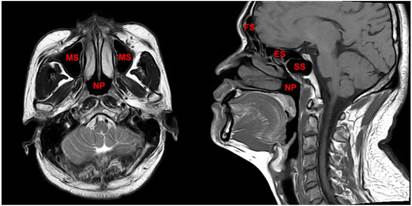

The region from the suprasellar cistern to the suprasternal notch were examined with a 1.5-T MRI system (Signa CV/i; General Electric Healthcare, Chalfont St. Giles, United Kingdom). Firstly, axial, coronal and sagittal T1- weighted (repetition time [TR]/echo time [TE], 500-600 ms/10-20 ms), and axial T2-weighted (TR/TE, 4,000-6,000/95-110 ms) fast spin-echo MR images were obtained. Secondly, gadopentetate dimeglumine (0.1 mmol/kg; Magnevist, Schering, Berlin, Germany) was injected intravenously. Then axial and sagittal spin-echo T1-weighted and coronal spin-echo T1-weighted fat-suppressed sequences were obtained. Further details regarding MR imaging techniques in our center have been reported previously [9, 15]. All MRI scans were reviewed jointly by two radiologists with more than 10 years' experience in head and neck cancer MRI. Paranasal sinuses involvement was diagnosed using the following criteria: (1) extension of primary tumor into the sinus cavity with sinus wall destruction; and (2) the lesion in the sinuses had the same signal intensity characteristics as the primary tumor. [9] The anatomical sites of the paranasal sinuses are shown in Figure 1.

Figure 1

The paranasal sinuses, which include the sphenoid sinus, ethmoid sinus, maxillary sinus and frontal sinus, are important anatomical structures that surround the nasopharynx in the anterior and superior directions. Abbreviations: SS = sphenoid sinus; ES = ethmoid sinus; MS = maxillary sinus; FS = frontal sinus; NP = nasopharynx.